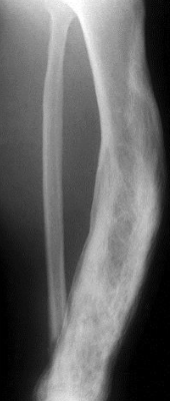

Paget’s disease of bone (Osteitis Deformans)

Chronic disorder of increased , but disordered bone mass due to disordered remodeling (rapid breakdown & faulty rebuilding) due to osteoclast dysfunction

Asymptomatic + X-ray as thick sclerotic coarse bone

Paget’s disease of bone Xrays

“Burnt out stage” - Pagetic bone typically are enlarged bone with thick, coarsened trabeculae – densely sclerotic bone

Mixed phase – osteosclerotic with osteolytic areas